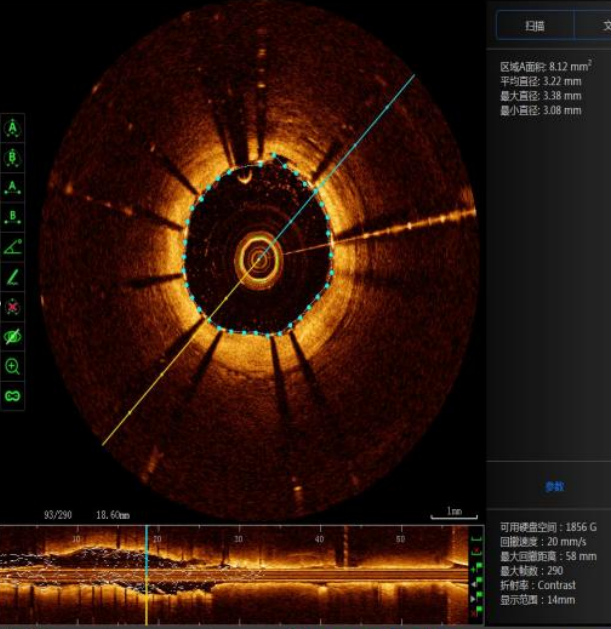

西南医科大学附属中医院成功开展医院首例新一代国产光学相干断层(OCT)检查指导下冠状动脉支架精准植入术近日,55岁的王先生因活动后心累、气促、头痛等症状,来到西南医科大学附属中医医院治疗,心血管内科医生接诊后为王先生完善了相关检查,找到了病...